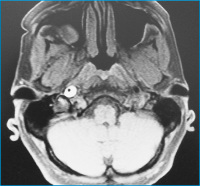

Horner-Syndrom

Abbildung 2: Zerebrales MRT in fettgesättigter T2-Gewichtung: Darstellung des halbmondförmigen Wandhämatoms der ACI rechts knapp oberhalb der Bifurkation bis in die Pars petrosa reichend bei einem 50jährigen Patienten (siehe Abb. 1), der nur mit einem Horner-Syndrom und Kopfschmerzen symptomatisch wurde (mit freundlicher Genehmigung von Dr. T. Gotwald, Radiologie II, Medizinische Universität Innsbruck)

Keywords: Horner-SyndromMRTNeurologie